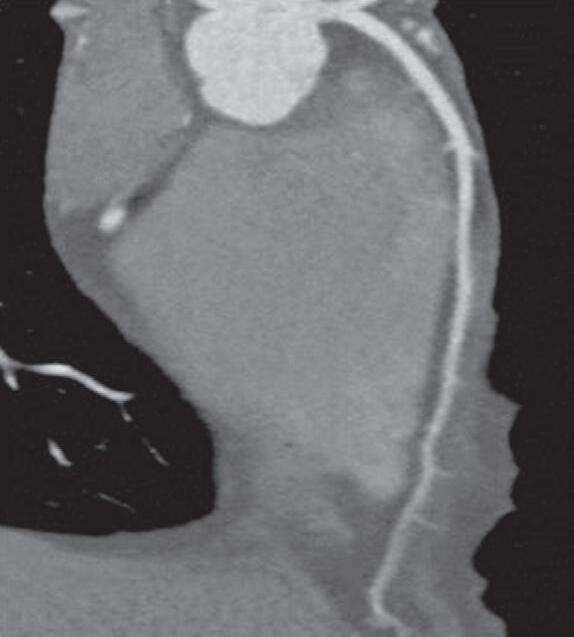

Fig. 15-8. (a) ultrassonografia (usG) de fígado cirrótico. (b,c) Correlação com a anatomia e a histologia.